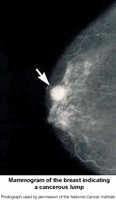

A mammogram is an X-ray image of your breast. It's used to find and diagnose breast disease. A mammogram may be done if you have breast problems such as a lump, pain, or nipple discharge. A mammogram is also done as a screening test if you don’t have breast problems. It can check for breast cancers, noncancerous or benign tumors, and cysts before they can be felt.

A mammogram can’t prove that an abnormal area is cancer. If a mammogram shows an area in your breast that is abnormal or may be cancer, follow up tests such as a breast ultrasound exam or an MRI may be done. For a conclusive diagnosis your healthcare provider removes a sample of breast tissue (biopsy) by needle or during surgery. The tissue will be examined at a lab under a microscope to see if it's cancer.

Breast cancer